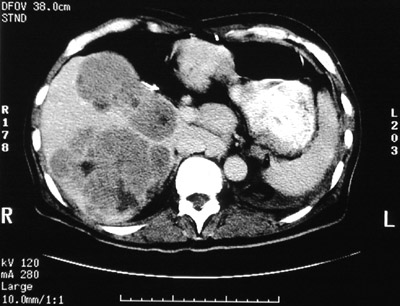

This abdominal CT scan demonstrates multiple variegated

mass lesions

, some with dark

central necrosis

, in a patient with widespread metastatic carcinoma. A

normal sized spleen

is seen at the lower left.